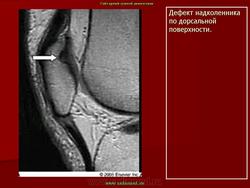

ХОНДРОПАТИЯ НАДКОЛЕННИКА (болезнь Левена). Этиология и патогенез. Чаще всего развивается после мелких повторных травм надколенника (у футболистов, бегунов, баскетболистов и т. д.), значительно реже — после однократной сильной травмы.